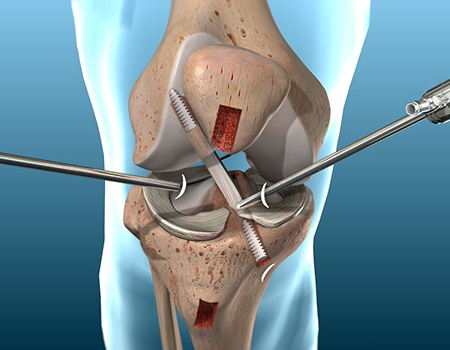

Ligament Surgery